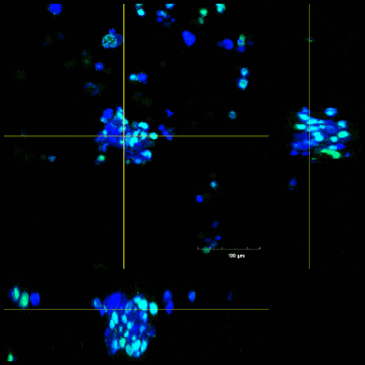

HER2遺伝子の発現量

- 青…DAPI

赤…HER2(トラスツマブにより染色) - 抗体医薬陽性容積を算出

- 細胞塊のHER2は局所的に発現が見られる

- リアルタイムPCRのよるHER2遺伝子の発現量の測定では、F-PDO®間での差異は大きくなかったが、免疫染色ではF-PDO®間での発現のパターンに違いがある。

- 固形がん組織の発現パターンに近い状態であるため、F-PDO®を用いることでより良い薬効評価が行われる。

| 肺がん | ||

|---|---|---|

| RLUN5 | RLUN16 | RLUN21 |

![]() |